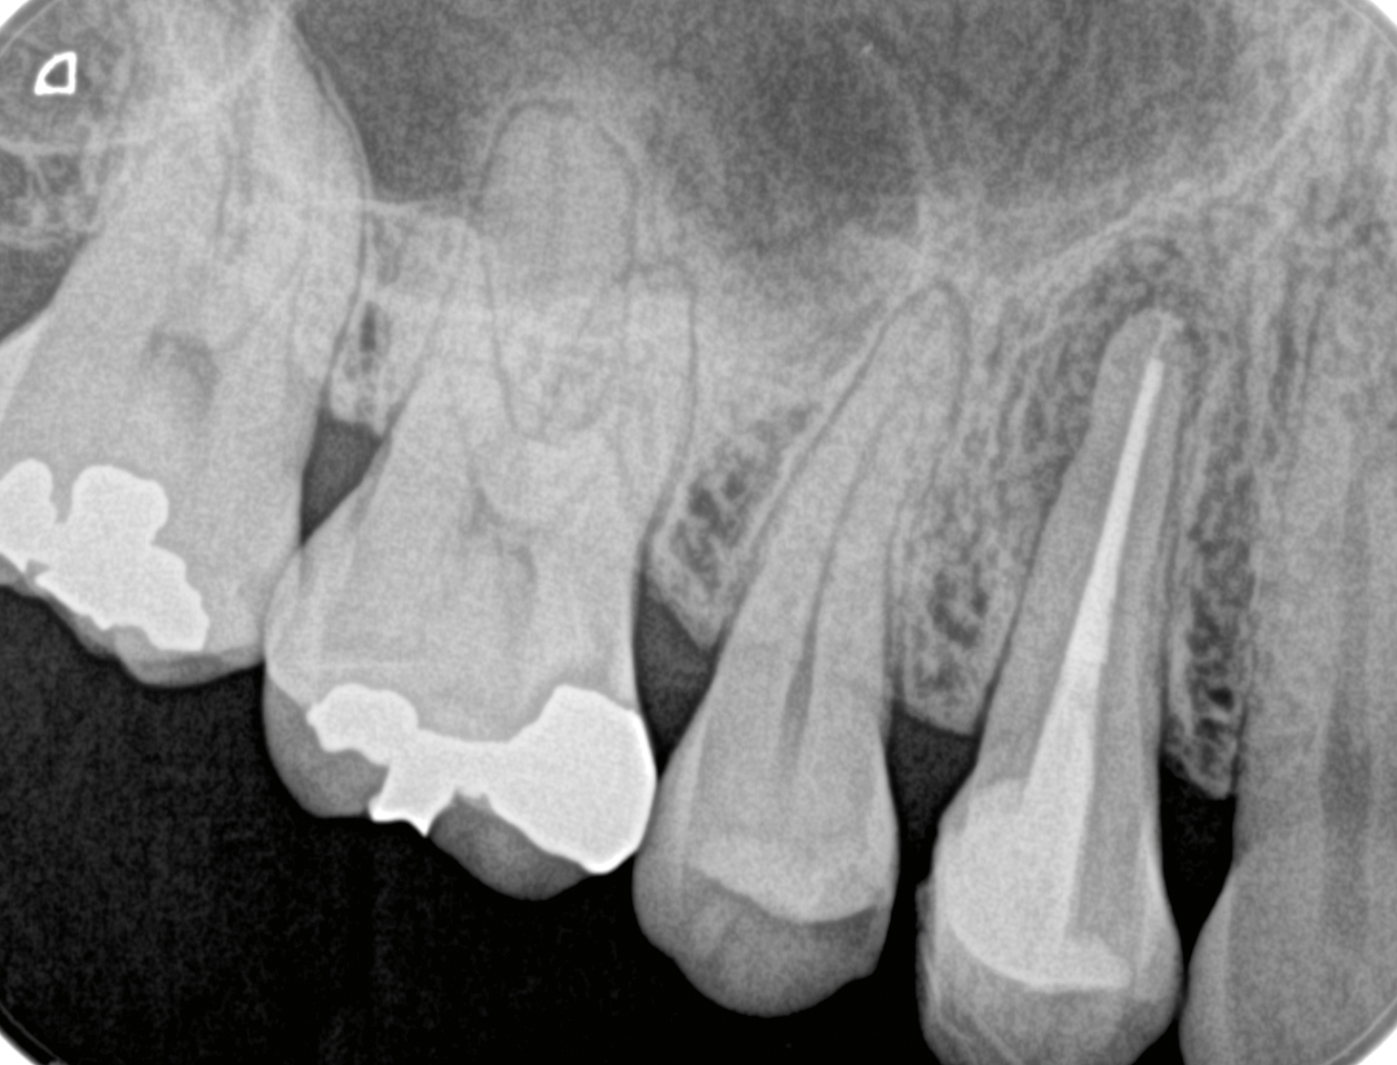

根管充填、支台築造終了時。グラスファイバーはアンジェラスホワイトポスト1.1mmとホワイトピンを使用した。